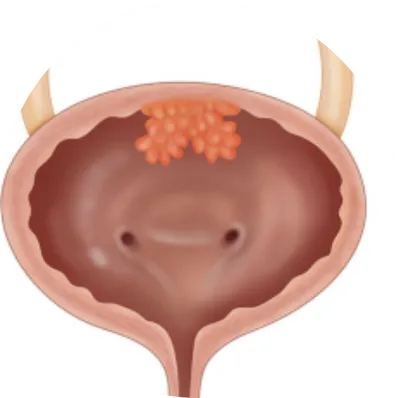

Cystectomy is a major surgical procedure to remove part (partial cystectomy) or the entire bladder (radical cystectomy). It is most often performed for muscle-invasive bladder cancer or high-risk recurrent bladder tumors. In men, it may include removal of the prostate and seminal vesicles; in women, the uterus, ovaries, and part of the vagina may also be removed. A new way for urine storage and drainage (urinary diversion) is created after surgery.

Types of Cystectomy

Only the diseased portion of the bladder is removed. Suitable for selected patients with limited, localized tumors.